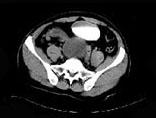

问题 男,34岁,右下腹持续性隐痛半月,排尿时加重入院,CT检查如图所示,下列说法错误的是 ( )

选项 A、该囊性病变考虑来源于精囊 B、此囊性病变为右精囊腺囊肿 C、膀胱右后下方囊性病变 D、膀胱向下,向后移位 E、右肾缺如

答案 D